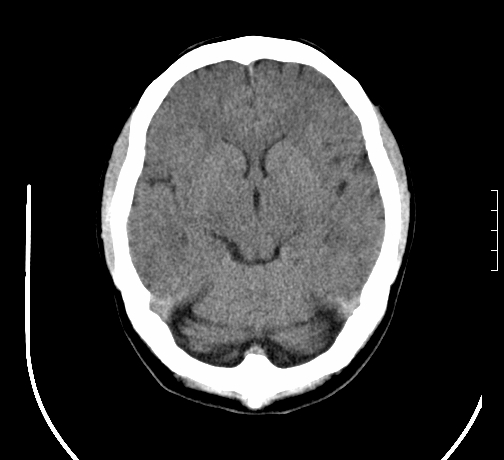

女,28岁,幼时有癫痫,常有发作,服药后可几月不发作,走路不稳3-4月,加重一月。

小脑发育畸形?

小脑萎缩。

考虑小脑发育不良,建议mri检查。

患者出现走路不稳是近几个月的事,而癫痫则有幼时就有,常发,则会常服药,癫痫药可引起小脑综合症,小脑萎缩,而小脑发育不良的主要症状不是癫痫

考虑癫痫,长期间断发服抗癫药,导致小脑综合症,小脑萎缩

考虑小脑发育不良伴小脑萎缩,建议mri检查。

小脑萎缩,原因待查,建议mri检查。

考虑小脑发育不良伴小脑萎缩,建议mri检查

考虑药物性小脑萎缩